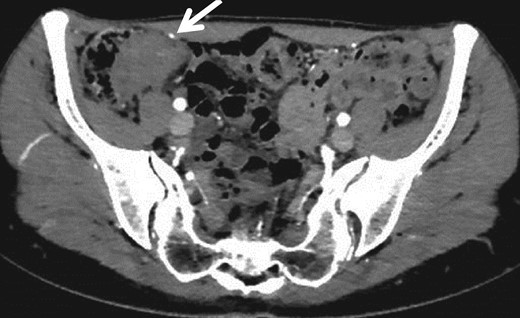

A 30-year-old woman underwent left ovariectomy and right ovarian endometrioma resection. At 40 years old, she noticed hematochezia and right-lower abdominal pain during menstruation, the symptoms continued over 3 years. At 43 years old, although she no longer noticed the same symptoms, she had right-side chest and back pain during menstruation so visited the doctor. A tumor of the ileocecum and right pneumothorax were discovered by computed tomography (CT). Pneumothorax was improved by conservative treatment. Submucosal tumor (SMT) was discovered at the rectosigmoid (RS) by colonoscopy (CS). The patient was referred to our hospital. A 3 cm size mass was discovered in the right-lower abdomen. Rectal examination was unremarkable and laboratory data was normal. CS showed the SMT with erosion at RS (Fig. 1a). As the scope could not pass through the sigmoid colon, we used the double balloon endoscopy. We observed erythrogenic mucosa of the ileum resembling salmon roe (Fig. 1b), and the cecum was suppressed from the outside. Biopsy was taken from the RS and ileum, but the pathological result was benign. Endoscopic ultrasound guided fine needle aspiration was also performed from the RS, but no abnormal cell were observed. By abdominal CT, a mass lesion was recognized at the ileocecum. No abnormal lesions were recognized at the rectum (Fig. 2).

Specimen: Strong dimpling of the serosa on rectum and ileocecum was recognized (Figs 3a, b and 4a, b).

(a) Resected specimen (ileocecum): Serosal dimpling was also observed. (b) Resected specimen (ileocecum): A SMT-like lesion was also observed.